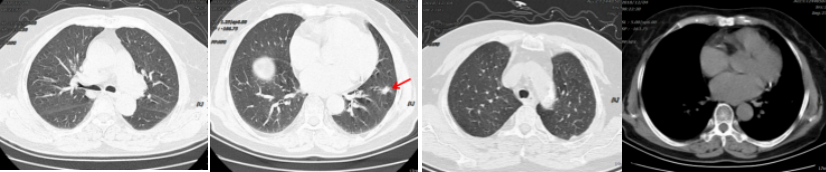

病例简介 该病例是一个肺腺癌(cT4N0M1a)IVa期患者,合并有高血压、冠心病、糖尿病。一线治疗前基因检测结果提示EGFR 19del(+)。一线治疗(埃克替尼片125mg tid)疗效评估为PR、PFS 22个月。一线治疗前基因检测结果提示EGFR 19Del(+)、T790M(+)。后入组D0316(贝福替尼)在EGFR阳性局部晚期或转移性非小细胞肺癌的II期临床试验(IBIO-102项目)。治疗先后由D0316 75mg qd更改方案为D0316 100mg qd,疗效评估为PR,、PFS>32月。至今患者仍持续用药随访中。 Part 1 基本信息 患者:女性;74岁。 主述:反复咳嗽3年,加重伴呼吸费力4月,于2018-1-17就诊。 既往史: 高血压病史10年,服用络活喜、厄贝沙坦氢氯噻嗪、美托洛尔控制血压;冠心病,冠脉支架置入术后4年;糖尿病史2年;否认其他病史。 Part 2 诊疗经过 治疗前辅助检查 2018-1-17查体:血压129/85mmHg;无明显阳性体征。 实验室检查 2018-1-18:血CEA 9.9ng/ml、Cyfra21-1 4.3ng/ml;SCC、NSE、Pro-grp均正常;血常规(Hb 109g/l)、肝肾功能、crp正常。 影像学检查 2018-1-8胸部CT:两肺多发结节,考虑MT伴转移,对照2017-10-4片增大,冠脉钙化,左侧部分肋骨陈旧性骨折,胆囊结石; 2018-1-22腹部B超:脂肪肝倾向,胆囊结石,两肾囊肿,两侧肾上腺未见明显异常回声; 2018-1-21头颅MRI:平扫+增强未见明显异常; 2018-1-23骨ECT:全身骨显像未见明显转移征象。 治疗前病理诊断 肺腺癌(cT4N0M1a) IVa期; 2018-1-18肺穿刺及病理:CK7( ++++ );NapsinA( ++++ ) ;TIF-1(++++);EGFR 19Del(+) ;ALK(-) 。 治疗前临床诊断 肺腺癌(cT4N0M1a) IVa期;PS 1分;EGFR 19Del(+);冠心病、冠脉支架置入术后;高血压病;糖尿病。 一线治疗 治疗方案:2018-1-26开始,埃克替尼片125mg tid。 疗效评估(PR,PFS 22月 ) 埃克替尼治疗11.3个月,两肺结节减少、缩小,达到PR (2018-12-4);治疗22个月,左下肺结节增大、肺内新发小结节、新发心包积液,出现PD(2019-11-21)。 2018-1-18 治疗前基线 2018-12-4 埃克替尼 11.3月(PR) 2019-11-21 埃克替尼 22月(PD) 一线治疗后辅助检查 实验室检查 2019-11-29血CEA 8.4ng/ml ;Cyfra21-1 4.8ng/ml;SCC、NSE、Pro-grp均正常。 2019-12-13血生化肌酐84umol/l;肝功能正常;血常规正常。 影像学检查 2019-12-4头颅MRI平扫+增强:脑内少许腔梗灶; 2019-12-2骨ECT:全身骨显像未见明显转移征象; 2019-12-4腹部增强CT:胆囊结石,右肾上腺及胰腺钙化灶,两肾囊肿。 生理学检查 2019-12-13 ECG:窦性心律,T波改变; 2019-12-13心超:左室轻度增大,左室壁偏厚,左房轻度增大,轻度肺动脉高压伴轻度三尖瓣返流,心包积液,脏层心包增厚,左室舒张功能轻度减退。 一线治疗后病理诊断 2019-11-29分子病理(ARMS法):EGFR 19Del(+) ;T790M(+)。 临床诊断 肺腺癌(cT4N0M1a);IVa期;肺、心包转移;PS 1分;EGFR 19Del(+);T790M(+);冠心病;冠脉支架置入术后;高血压病;糖尿病;肾功能不全。 二线治疗 入组D0316(贝福替尼)在EGFR阳性局部晚期或转移性非小细胞肺癌的II期临床试验(IBIO-102项目)。 治疗方案 2019-12-19开始D0316 75mg qd,于2019-12-24至2020-1-15出现头痛、肩背痛1级AE,自行缓解; 2020-1-13开始D0316 100mg qd; 合并用药有针对糖尿病药物西格列汀片 50mg qd;针对高血压药物氨氯地平5mg qd、厄贝沙坦氢氯噻嗪片1片qd、美托洛尔缓释片47.5mg qd;针对冠心病药物西洛他唑 50mg bid;针对睡眠障碍药物氯硝西泮片1mg qn、艾司酉酞普兰片10mg qd、喹硫平片50mg qd。 安全性评估 疗效评估(PR, PFS>32月 ) D0316 治疗6周就达到PR,患者左下肺靶病灶缩小,两肺小结节稳定、部分缩小(2020-1-28);治疗30周仍为PR,且心包积液减少(2020-7-13);治疗30.5月仍为PR,右下叶背段胸膜下结节缓慢进展(2022-6-30)。 2019-11-21 D0316 治疗前基线 2020-1-28 D0316 治疗6周(PR) 2020-7-13 D0316 治疗30周(PR) 2022-6-30 D0316 治疗30.5月(PR) 2022-6-30腹部增强CT:胆囊结石,右肾上腺及胰腺钙化灶,两肾囊肿。 目前D0316(贝福替尼) 100mg qd 治疗中, PS 1分。